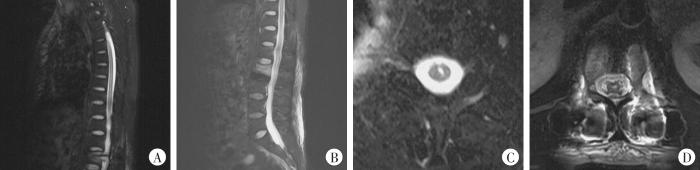

5月13日转入某市人民医院。既往无糖尿病、高血压及感染病史。入院查体:深、浅感觉正常,四肢肌力、肌张力正常,神经生理反射存在,病理反射未引出。腰椎MRI及CT片示:L2椎体压缩性骨折并骨挫伤(骨髓水肿)改变,压缩程度约1/3,骨折累及椎体前、中柱,附件未见确切骨折征象,相应节段椎管未见骨性狭窄,脊髓圆锥未见确切急性损伤信号(图1A);胸主动脉未见明显钙化,腹主动脉管壁钙化(图1B)。入院后完善相关辅助检查:甘油三酯2.10 mmol/L(正常参考值0.45~1.81 mmol/L)、胆固醇7.80 mmol/L(正常参考值2.07~3.10 mmol/L)、低密度脂蛋白5.02 mmol/L(正常参考值2.07~3.10 mmol/L),予匹伐他汀钙片降脂。无绝对手术禁忌证,告知患方保守治疗、切开复位椎弓根螺钉内固定术及有限切开椎弓根螺钉内固定术等治疗方案的优缺点,患方选择有限切开椎弓根螺钉内固定术治疗。于5月17日17:30—19:50在全身麻醉下行“L2椎体爆裂骨折经皮有限切开椎弓根螺钉内固定术”,麻醉用盐酸格拉司琼注射液、盐酸右美托咪定注射液、枸橼酸舒芬太尼注射液、注射用苯磺顺阿曲库铵、丙泊酚乳状注射液、羟乙基淀粉130/0.4氯化钠注射液,吸入医用七氟烷,术中在C臂透视下植入椎弓根螺钉,螺钉位置满意,骨折复位良好,术中失血50 mL。术中血压(16.0~20.0)/(9.3~12.0) kPa[(120~150)/(70~90) mmHg]、呼吸19~20次/min。术后麻醉恢复平稳,血压(16.8~19.2)/(8.3~12.1) kPa[(126~144)/(62~91) mmHg],麻醉苏醒后诉手术切口疼痛,未诉肢体无力等不适。术后约11 h突发右侧胸背部剧烈疼痛,躯体左侧乳头平面以下痛觉、温度觉消失,但触觉、本体感觉正常,左侧提睾反射、肛周反射减弱,左下肢肌力、感觉减退,左侧髂腰肌、股四头肌、胫前肌肌力0级,左侧屈拇趾肌力4级,余各足趾不能屈曲,病理征阴性,膝腱反射、跟腱反射未引出,导尿管通畅,右侧腹壁反射、提睾反射、肛周反射、膝踝反射正常,双上肢及右下肢肌力、肌张力、感觉正常。术后第2天复查全脊髓MRI示:L1~L3椎弓根螺钉内固定术后改变,内固定位置正常,椎管内无异常占位,T3水平以下胸腰段脊髓见散在节段性T1等信号影、T2高信号影,横断面上见T2高信号影位于脊髓偏左侧,颈髓未见异常信号影,胸段及上腰段未见椎间盘突出、椎体骨赘增生等退行性变(图2)。颅脑MRI未见异常。经多学科疑难病例讨论及上级医院远程会诊后考虑脊髓前动脉综合征,予以扩张血管、改善局部微循环、预防血栓、激素抗感染、脱水消肿及营养神经等对症治疗。术后第3天拔除尿管后二便可,术后第6天患者右侧胸背部剧烈疼痛明显缓解,股四头肌肌力1级,左侧髂腰肌、胫前肌肌力0级,左侧屈趾肌力约4级,余持续无明显改善。术后第22天复查甘油三酯2.38 mmol/L、胆固醇7.48 mmol/L、低密度脂蛋白4.53 mmol/L。

图2

图2

术后第2天全脊髓MRI影像

A:胸段脊髓矢状面见节段性T2高信号影;B:腰段脊髓矢状面见节段性T2高信号影;C:胸段脊髓横断面见病灶位于脊髓偏左侧;D:椎弓根螺钉内固定位置正常,腰段脊髓内见T2高信号影,病灶偏左侧。

Fig. 2

MRI images of the whole spinal cord on the postoperative day 2

同年8月22日转入某上级医院。入院查体:躯体左侧自乳头平面以下痛觉、温度觉减退,触觉、深感觉正常;左下肢肌力1-级,肌张力降低,各腱反射未引出;右下肢及双上肢肌力、肌张力均正常,各腱反射活跃;病理征阴性。全脊髓MRI示:T3平面以下胸腰段脊髓、圆锥散在节段性T2高信号影,横断面示病灶位于脊髓偏左侧,颈髓未见异常信号影。入院后完善腰椎穿刺检查未见异常,予对症治疗。

复阅术后第2天及3个月余全脊髓MRI片示:L1~L3椎弓根螺钉内固定术后改变,内固定位置正常,椎管内无异常占位,T3水平以下胸腰段脊髓、圆锥见散在节段性T1等信号、T2高信号影,横断面上见T2高信号影位于脊髓偏左侧,呈“独眼龙”征象,颈髓未显示异常信号影。

本例特异性临床表现及MRI影像学表现与ASAS的临床特征相符,患者自身存在高脂血症、主动脉钙化等ASAS危险因素,说明本例符合自发性ASAS致左下肢单瘫,但由于本例胸段及上腰段未见椎间盘突出、椎体骨赘增生等退行性变,亦未行主动脉和脑血管CTA或MRA检查,其具体发病原因不明。临床报道的ASAS致肢体瘫痪多为四肢瘫或截瘫且常伴大、小便功能障碍[9]。理论上,一侧沟连合动脉阻塞可能导致脊髓横断面前2/3的半侧梗死引起单肢瘫,但一支沟连合动脉供血节段有限,如本例长节段性脊髓半侧梗死,其原因可能是某些人群存在两条脊髓前动脉供应脊髓全段[2],此亦为本例无大小便功能障碍且脊髓横断面MRI影像学表现呈“独眼龙”而非典型“蛇眼征”的原因。